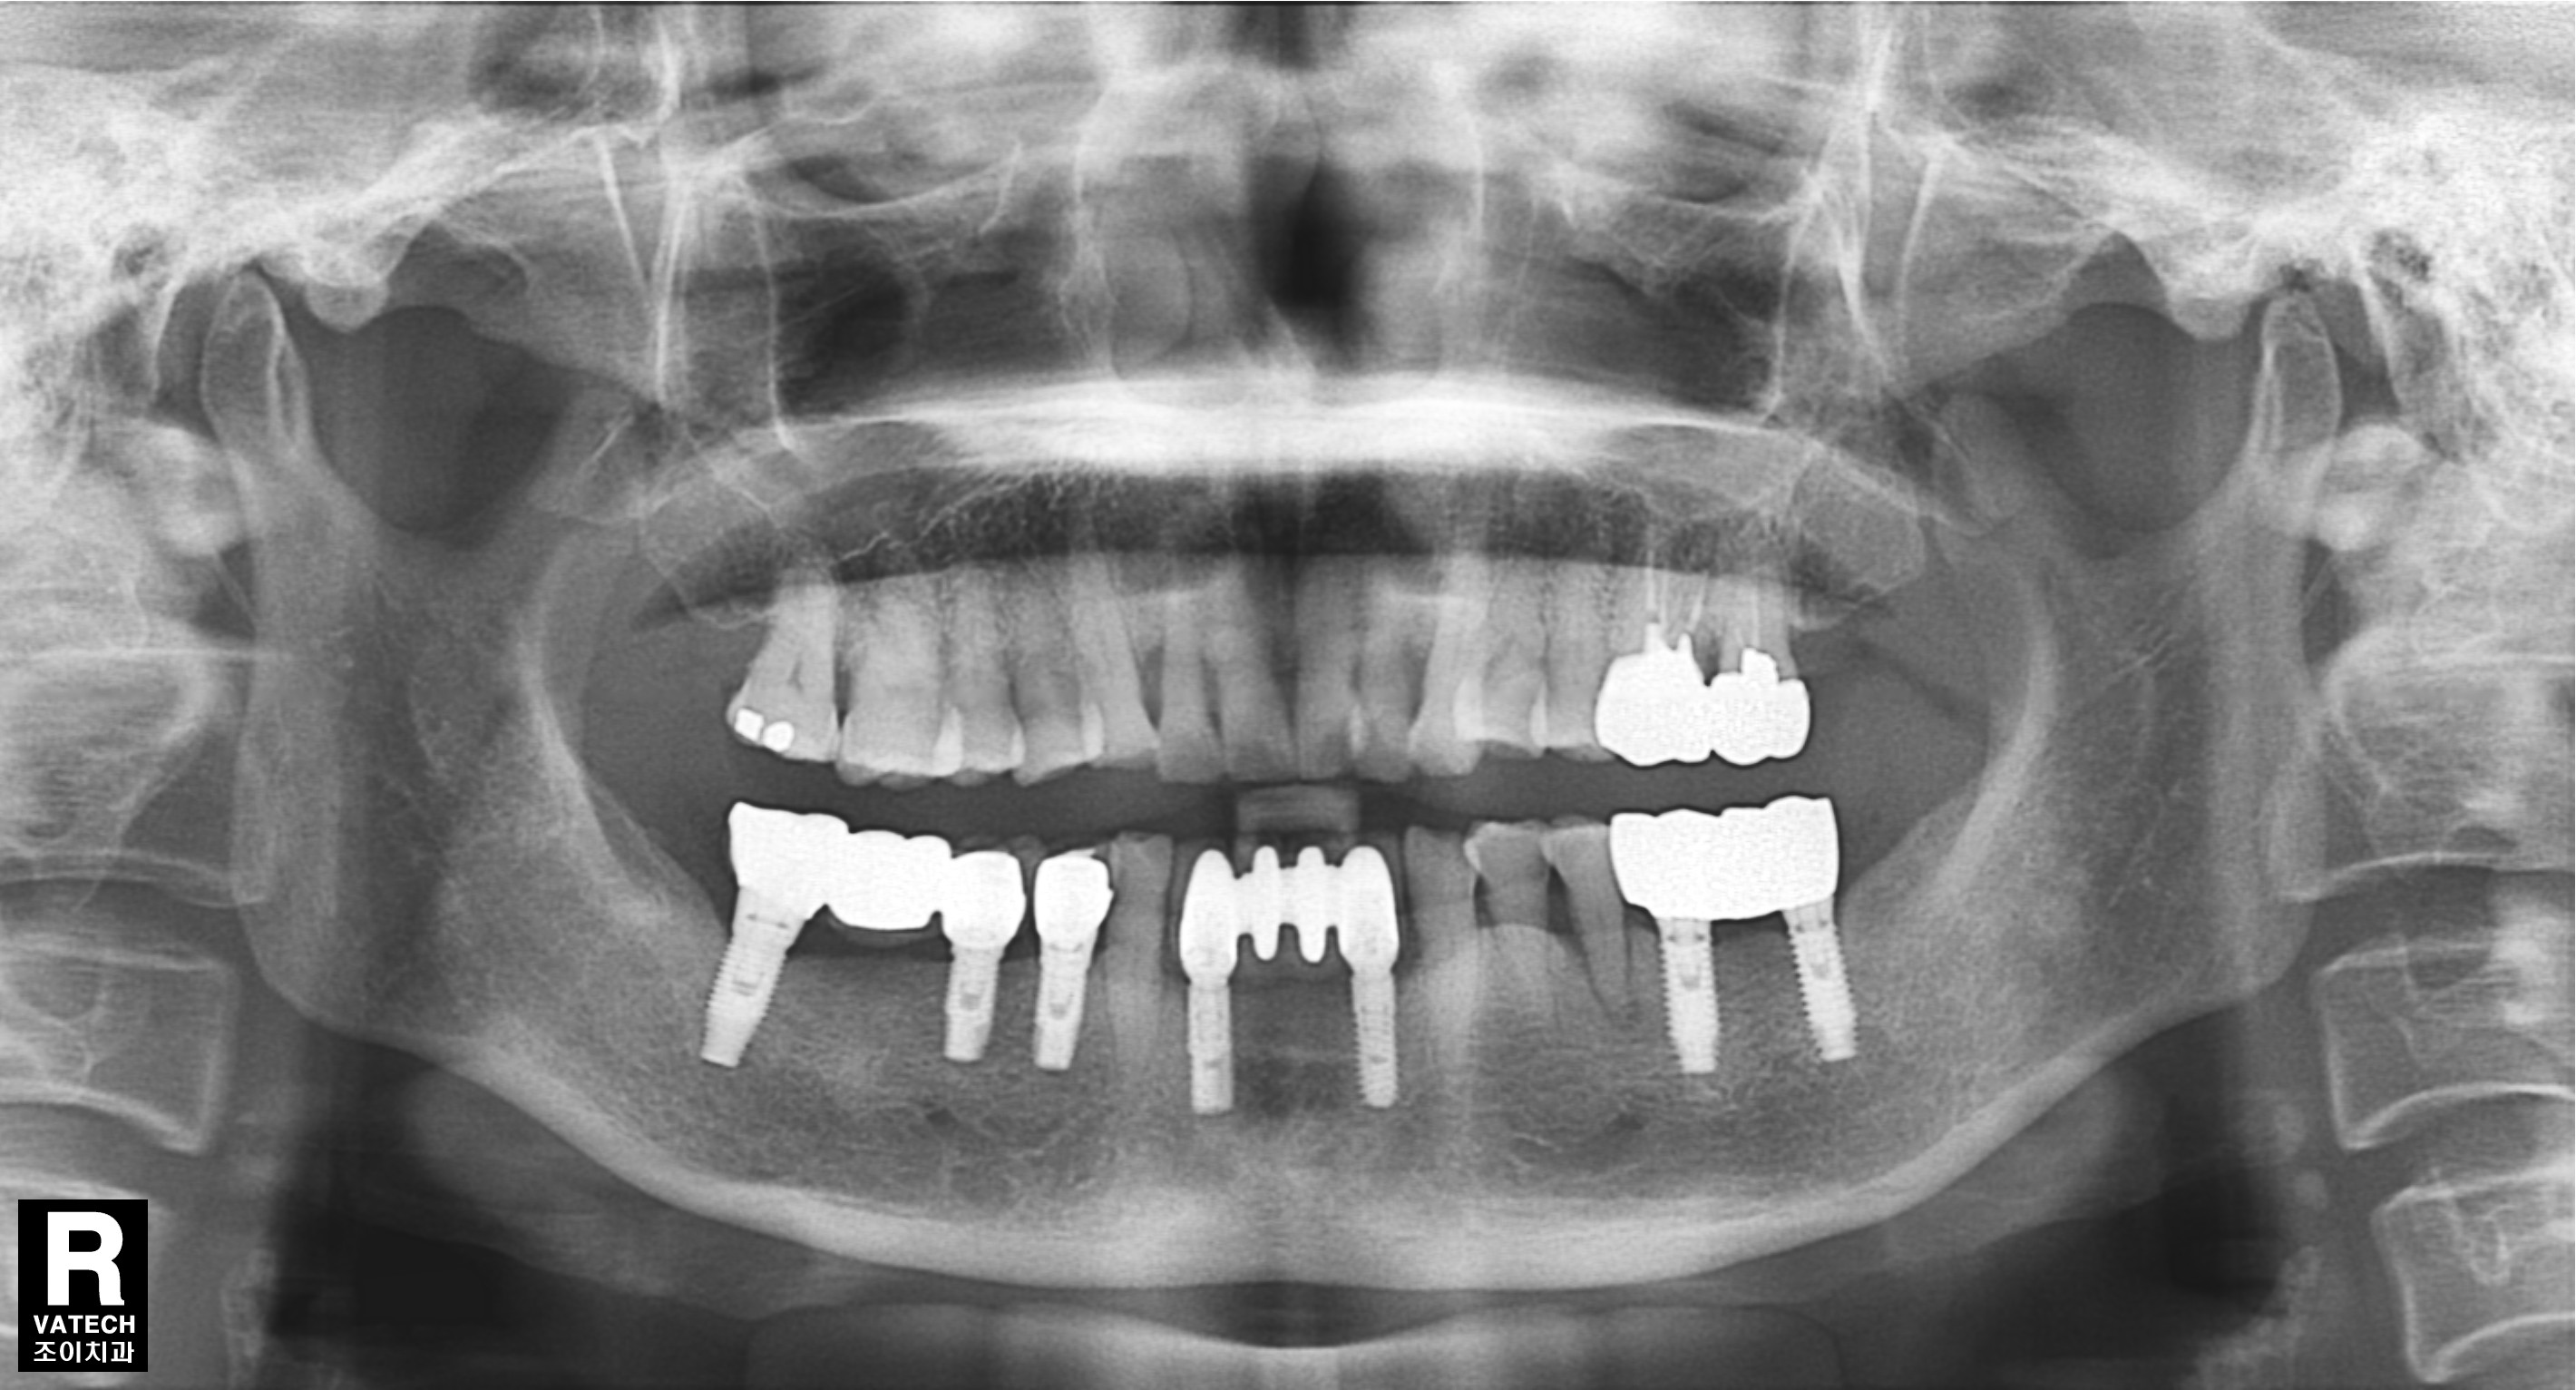

[임플란트] 제목 : 하악전치

임플란트 보철